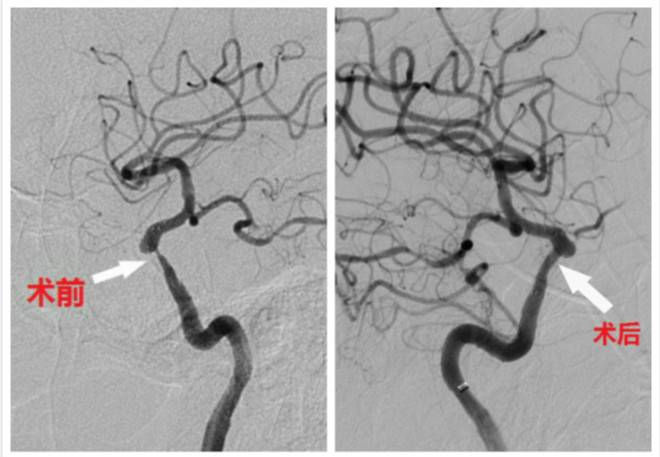

近日,我院神经内科介入团队紧跟国际前沿,对1例颈内动脉床突段支架后再狭窄患者实施DBC手术,并获得了满意的效果。

患者马某,59岁,既往有糖尿病、高血压及吸烟史,长期喜欢静坐、不运动,半年前因脑梗死左侧肢体无力行右侧颈内动脉床突段支架置入术,术后患者未遵医嘱控制血糖,空腹经常在10 mmol/L以上,餐后最高血糖30mmol/L,未戒烟,且长期久坐不运动。近日脑梗死复发,复查脑血管造影提示原支架内再狭窄。在经过周密的文献回顾、国内相关专家会诊讨论后,于2019年1月8日由二附院张桂莲教授、展淑琴教授在全麻下给予支架内再狭窄部位DCB扩张术,手术顺利,目前患者病情逐渐好转。